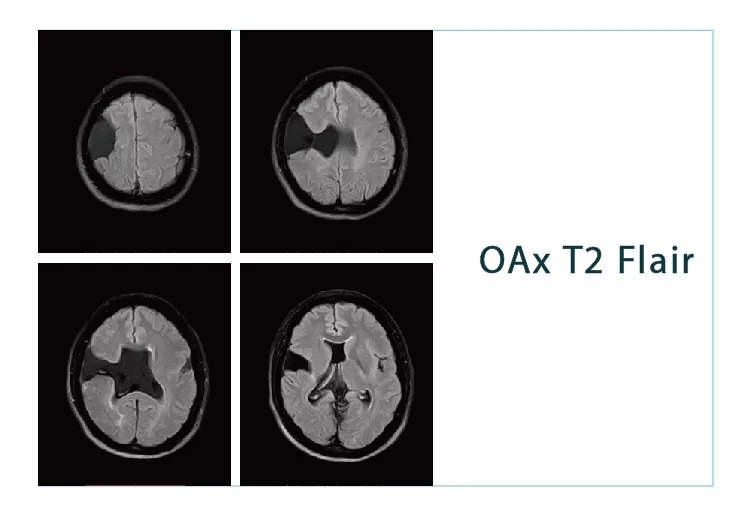

【朗润影像档案】20180824磁共振影像病例结果讨论